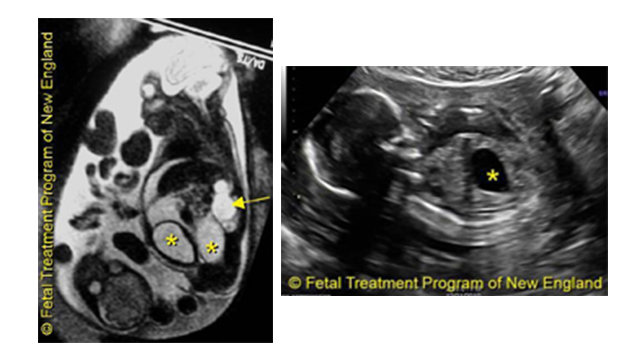

Examples of Urinary Tract Obstructions

Left: Bladder obstruction: the bladder (*) is very distended, and there is no amniotic fluid around the fetus.

Right: Urinary obstruction: the kidney is very distended (arrow), and loops of very dilated ureter (*) are visible.